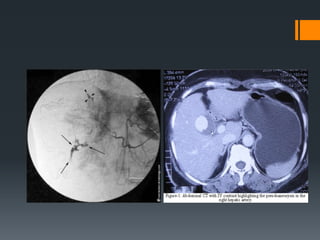

Liver Trauma

Bile duct injury

https://radiopaedia.org/cases/traumatic-liver-and-bile-duct-

injuries